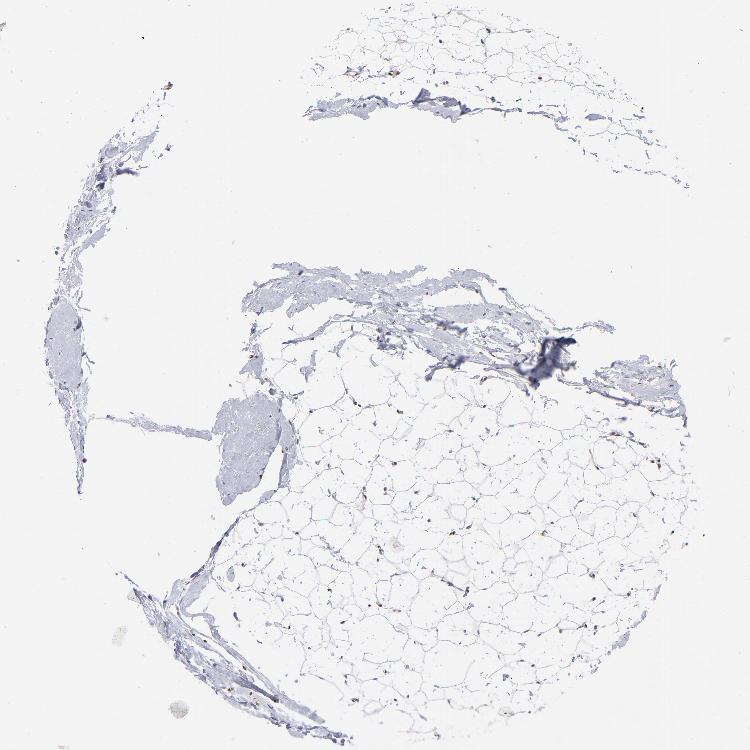

BREAST - Antibody stainingi

Antibody staining in the annotated cell types in the current human tissue is reported as not detected, low, medium, or high, based on conventional immunohistochemistry profiling in selected tissues. This score is based on the combination of the staining intensity and fraction of stained cells.

Each image is clickable and will lead to virtual microscopy that enables deeper exploration of all samples and also displays staining intensity scores, fraction scores and subcellular localization as well as patient and tissue information for each sample.

Antibody HPA003258Antibody HPA028791Antibody CAB004411

Adipocytes Not detectedMediumLow

Glandular cells MediumMediumNot detected

Myoepithelial cells MediumMediumNot detected